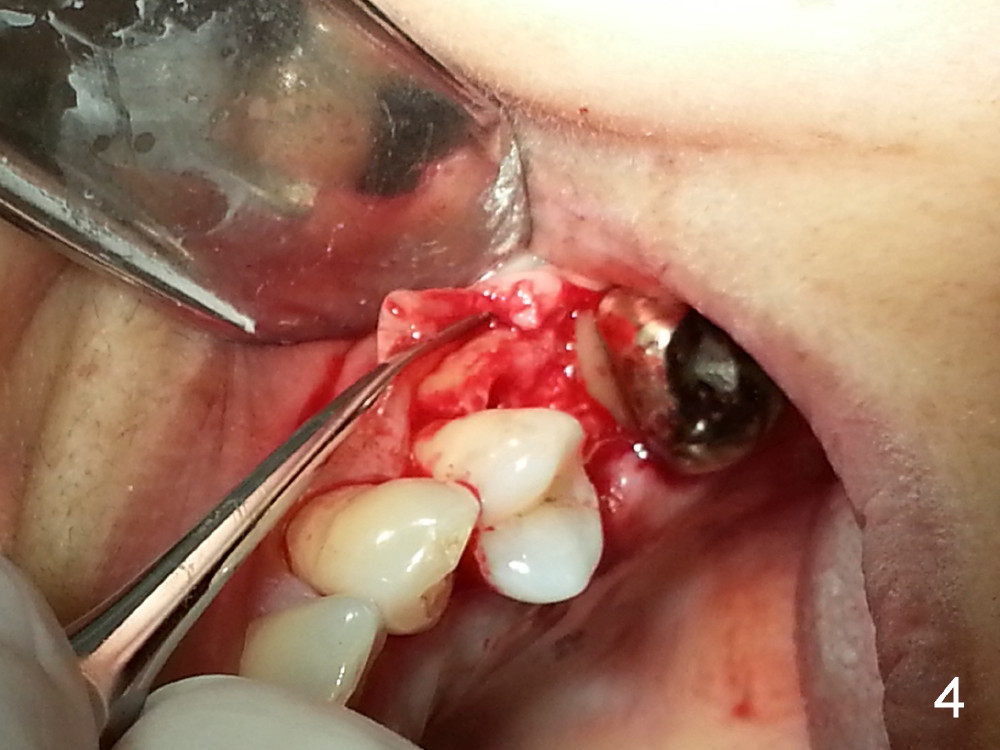

The tooth #13 appears to be affected by periodontits and occlusal trauma (Fig.1*). After using a periotome (Fig.2), the tooth is extracted (Fig.3). The buccal flap is raised (Fig.4). Gingival graft is to be harvested from the site of #15 (Fig.5). The tissue is elevated buccally (Fig.6) and separated (Fig.7). The donor site is covered by a collagen membrane (Fig.8*). A diamond bur is used to induce bleeding from the socket (Fig.9*). Osteotomy is initiated (Fig.10) and enlarged (Fig.11,12). A tapered implant is being placed (Fig.13-15) following internal sinus lift (Fig.16,17). The implant is placed subcrestally, followed by bone graft (Fig.18), soft tissue graft (Fig.19), and suturing (Fig.20 <, Fig.21).